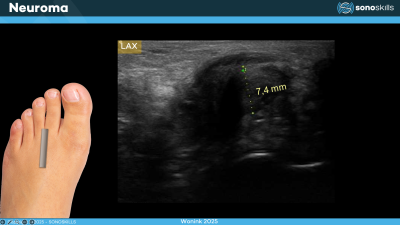

1. Morton’s neuroma

Morton’s neuroma is a benign enlargement of the plantar digital nerve usually located between the third and fourth metatarsal heads. Ultrasound can demonstrate a hypoechoic mass in the intermetatarsal space. In experienced hands ultrasound has good diagnostic accuracy and can also be used to guide corticosteroid or alcohol injections.